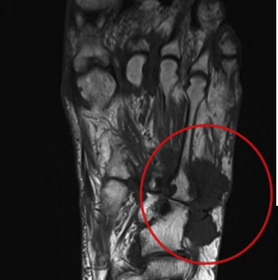

What does this indicate? | Increased signal and enhancement of the soft tissue plantar to the proximal phalanx suggestive of subcutaneous infection without abscess |

What does this indicate? | Increased signal and soft tissue distension dorsally representing subcutaneous abscess communicating with associated with plantar ulcerative defect. |